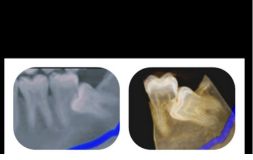

The tooth removal process depends upon the stage in which the wisdom teeth is. It is easy to extract wisdom tooth if it has fully erupted. But if the tooth is impacted then it will require an incision in the gums. Usually, the tooth is extracted in parts to minimize the amount of bone required to be extracted for tooth removal.